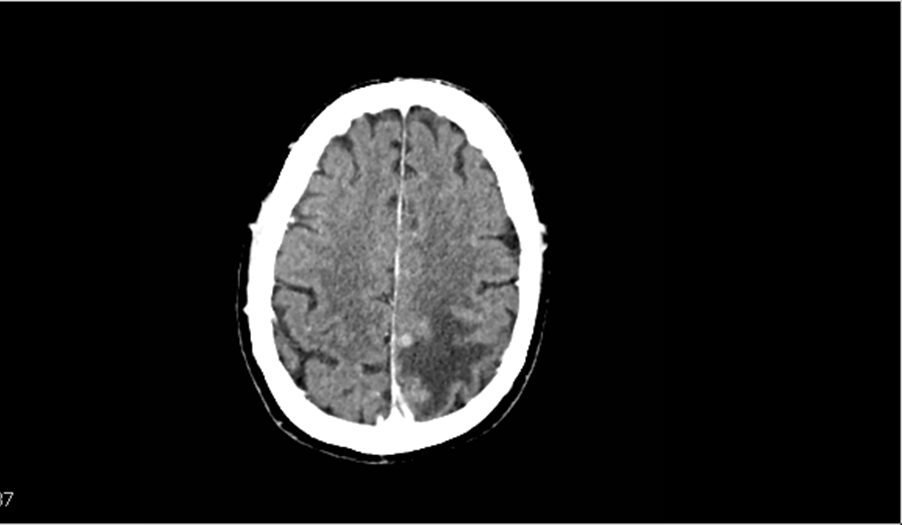

Vasogenic or cytotoxic edema?

Vasogenic edema

preserves the gray-white junction

This type of edema does not restrict diffusion, preserves the gray-white junction, and is not directly consistent with ischemia.

(cytotoxic edema blurs the gray-white junction, restricts diffusion, and is consistent with ischemia.